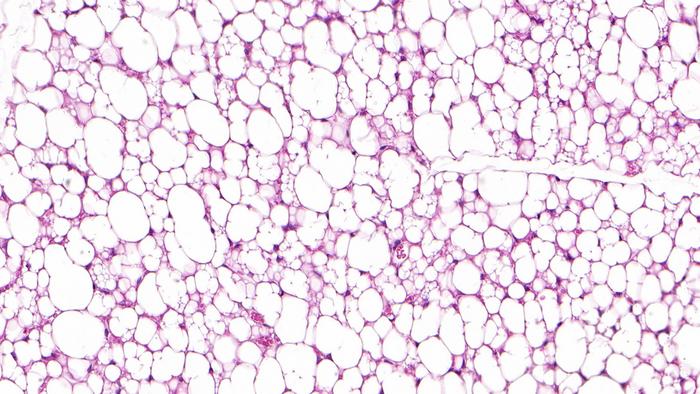

Fat cells come in three colours: white, brown, and beige. White fat cells store fat in our body as an energy reserve. We need these cells, but having too many creates health problems. Brown fat cells are particularly active in infants. They produce heat and thus maintain the baby’s body temperature. However, the amount of brown adipose tissue decreases over a person’s lifetime; adults have very little of it. Then, finally, the beige fat cells. These can also produce heat, albeit somewhat less well than brown fat cells. Beige fat cells occur in adults as well: scattered throughout the white fatty tissue, especially in the neck and shoulder area, they help in using up excess energy.

The research team first described the new type of beige fat cells in mice. They then examined human adipose tissue and were able to show that these fat cells occur there, too. While less than half the population has the previously known type of classical beige fat cells, almost all humans have the new futile-cycle type, albeit in differing amounts.